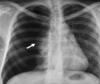

¿Qué es esto?

Neumotórax

¿Cómo se ve el neumotórax en Rx y TC?

- Hiperclaridad - Pérdida de trama vascular - Pulmón colapsado

50